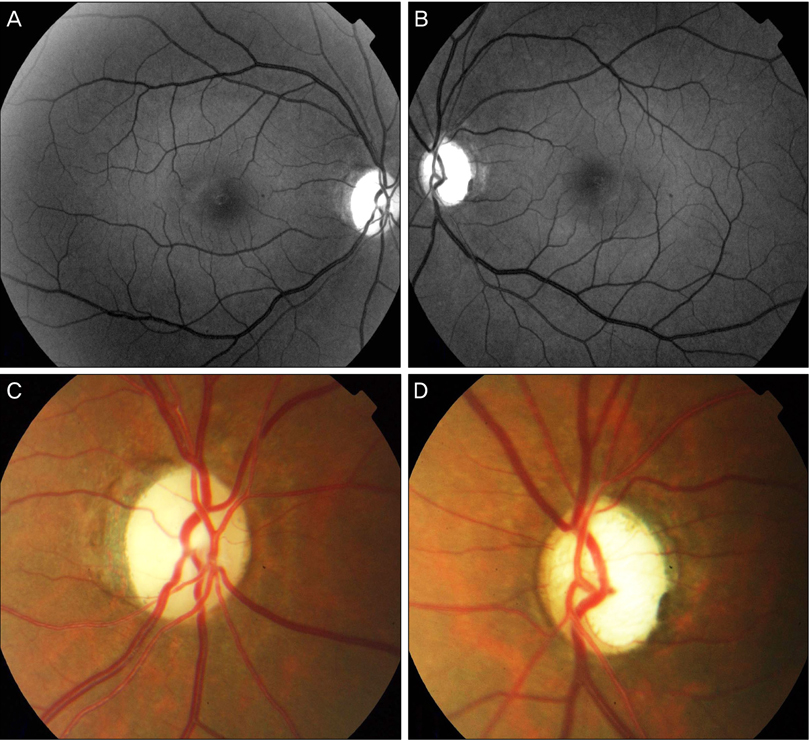

아래 사진의 좌측처럼 유두함몰은 크지 않으나, 시신경유두테가 창백해지는 경우는, 창백 > 함몰로써,

녹내장이 아닌 질환으로 인해서 시신경이 손상된것입니다.

아래의 우측사진의 경우, 시신경은 창백하지 않으나, 함몰이 발생하여, 아래쪽으로 함몰이 커져있습니다.

즉, 함몰 > 창백으로써, 전형적인 녹내장의 소견입니다.